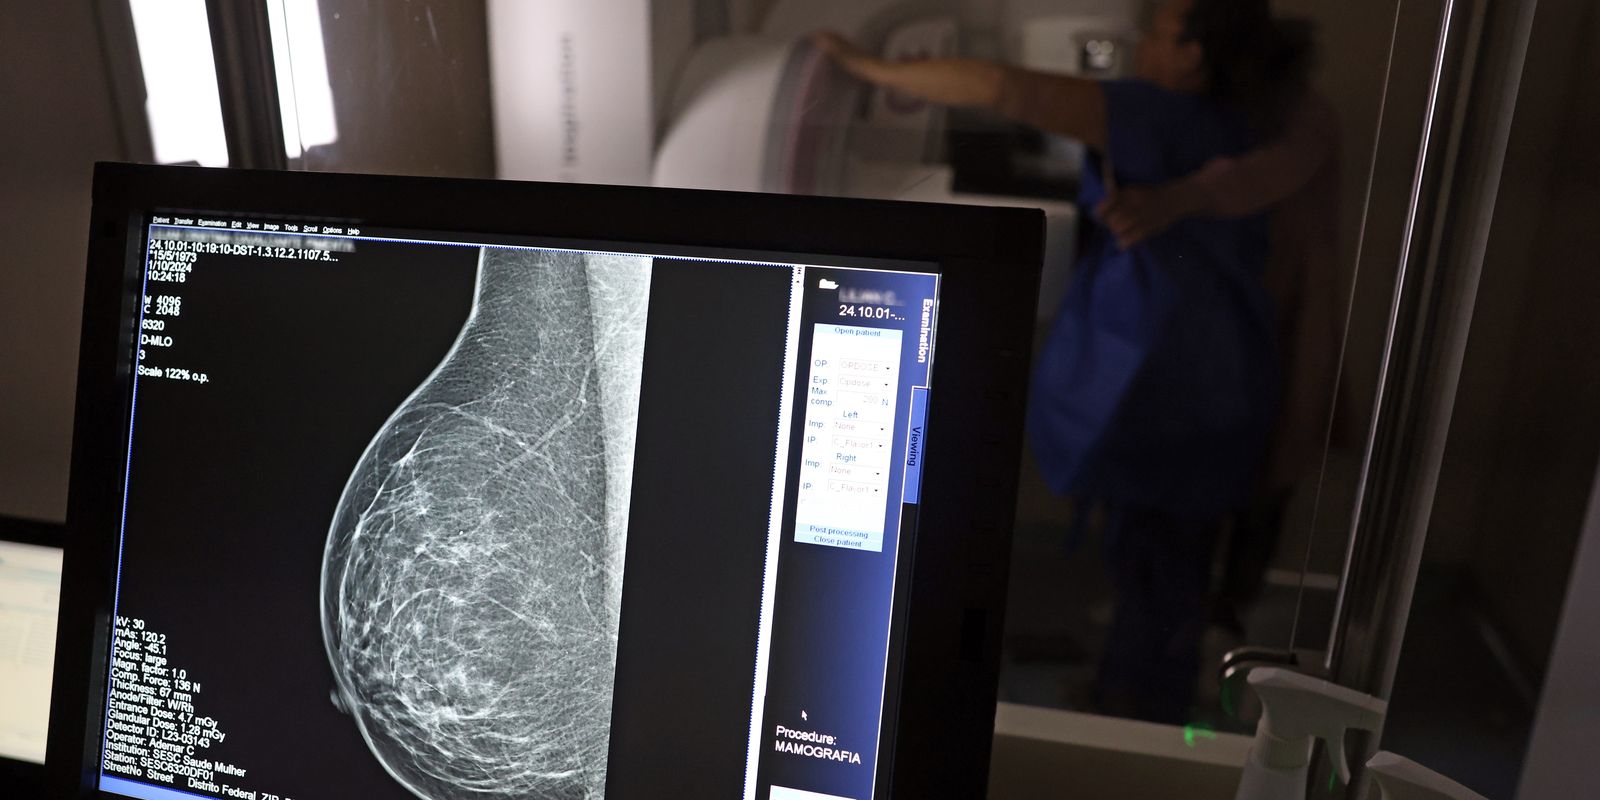

A partir de quantos anos se deve fazer a mamografia de rastreio, ou seja, como um exame de rotina, mesmo sem sintomas? Para autoridades públicas, como o Ministério da Saúde e o Instituto Nacional do Câncer (Inca), o ideal é que a mamografia seja feita a cada dois anos por todas as mulheres entre 50 e 69 anos. Algumas entidades médicas, como a Sociedade Brasileira de Mastologia (SBM), entretanto, recomendam exame anual a partir dos 40 anos.

A ANS decidiu, entretanto, seguir em sua minuta o protocolo do Inca, que também é adotado no Sistema Único de Saúde (SUS) e preconiza a realização de mamografia de rastreio apenas a partir dos 50 anos, com intervalo de dois anos entre os exames, caso nenhum problema seja encontrado. “O rastreamento do câncer deve ser direcionado às mulheres na faixa etária e periodicidade em que há evidência conclusiva sobre redução da mortalidade por câncer de mama e em que o balanço entre benefícios e possíveis danos à saúde dessa prática seja mais favorável”, diz a minuta.

Roberto Gil explica por que esses estudos consideram que os 50 anos são a idade certa para o início do rastreamento na população em geral: “Não estamos negando que mulheres abaixo de 50 anos tenham câncer de mama. Estamos falando que, abaixo dos 50 anos, acumulam-se outros problemas e o rastreamento populacional é menos eficiente. A mamografia é um exame de raio X, que vai ser mais efetivo na medida que a mama seja menos densa e que se tenha mais contraste na imagem, para não se confundir o parênquima normal com um nódulo. Então [antes dessa idade], aumenta muito mais a possibilidade de ter falsos positivos e ter que fazer mais exames. Posso fazer uma biópsia e ser mais difícil interpretar e levar a uma cirurgia desnecessária.”